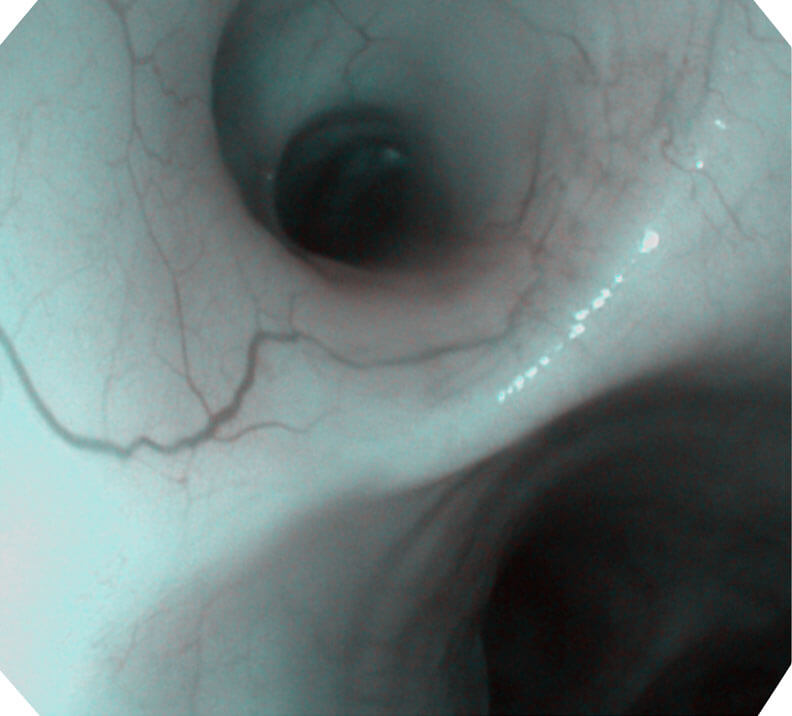

120°视场角,满足更大视野范围的观察。配合 VIST 染色,助力呼吸系统疾病的诊断。

光电复合染色成像技术(VIST)是一种光学滤波和数字滤波相结合的染色成像技术,摒弃了滤光转轮而直接采用光谱组合的方案,加入了血红蛋白吸收高峰与次高峰的蓝紫光和绿光光谱,更有利于黏膜血管吸收,突显浅表层血管和中层血管的对比度,因而具备更高的图像对比度,有助于观察微细结构变化及病灶边界的观察。